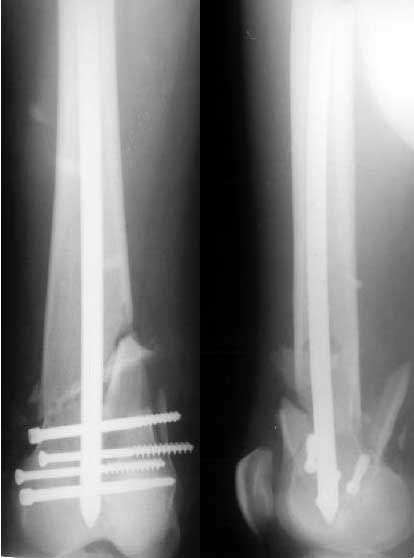

Такой вариант мы не рассматривали как чрезмерно травматичный. Как и предполагали, удалось сопоставить отломки стержня и после удаления

винтов вытолкнуть нижний кусок дистально. И через это же отверстие, используя стандартный доступ с расщеплением сухожилия 4-главой мышцы,

ретроградно забили другой стержень диаметром опять 11 мм - толще у нас пока таких нет. Обнадеживает то, что диаметр утолщенной части стержня 12 мм, а отверстие - 5 мм.

If we should look for "hairs in an egg", we can see that distal fragment is a little flexed and (perhaps) valgus.

First deviation could be corrected by removing at first the screw with black arrow.

Another little imperfection is the small size of the nail and large holes (see the other black arrows) just on the fracture line : these mechanically make the nail less resistant and, if weigh bearing is full, they could be a cause of failure.

If your patient will be prudent, fracture will heal very well.

You said: " but inserted from below. I locked it statically at the moment."

I have a query. From the picture it looks as if you used the usual proximal end as the distal end of nail.

This means that you would have got the help of the zig to lock the distal end(near the knee). If this is correct how did you lock the holes near the trochanter?